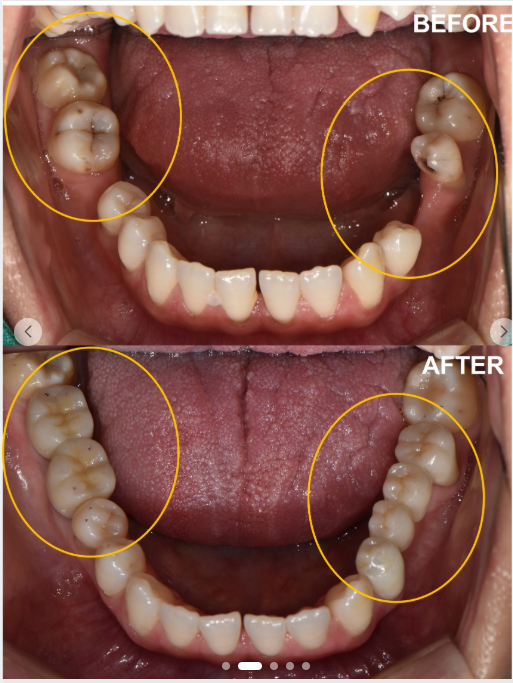

(60대 여성 임플란트 치료 사례)

다음으로 중요한 것은 나와 비슷한 치료 사례가 있는지 확인하는 것입니다.

"앞니가 빠진 경우",

"어금니 여러 개가 없는 경우",

"뼈가 많이 부족한 경우" 등

자신과 유사한 상황의 치료 과정과 결과를 사진이나 영상으로 설명해주는지 살펴볼 필요가 있습니다.